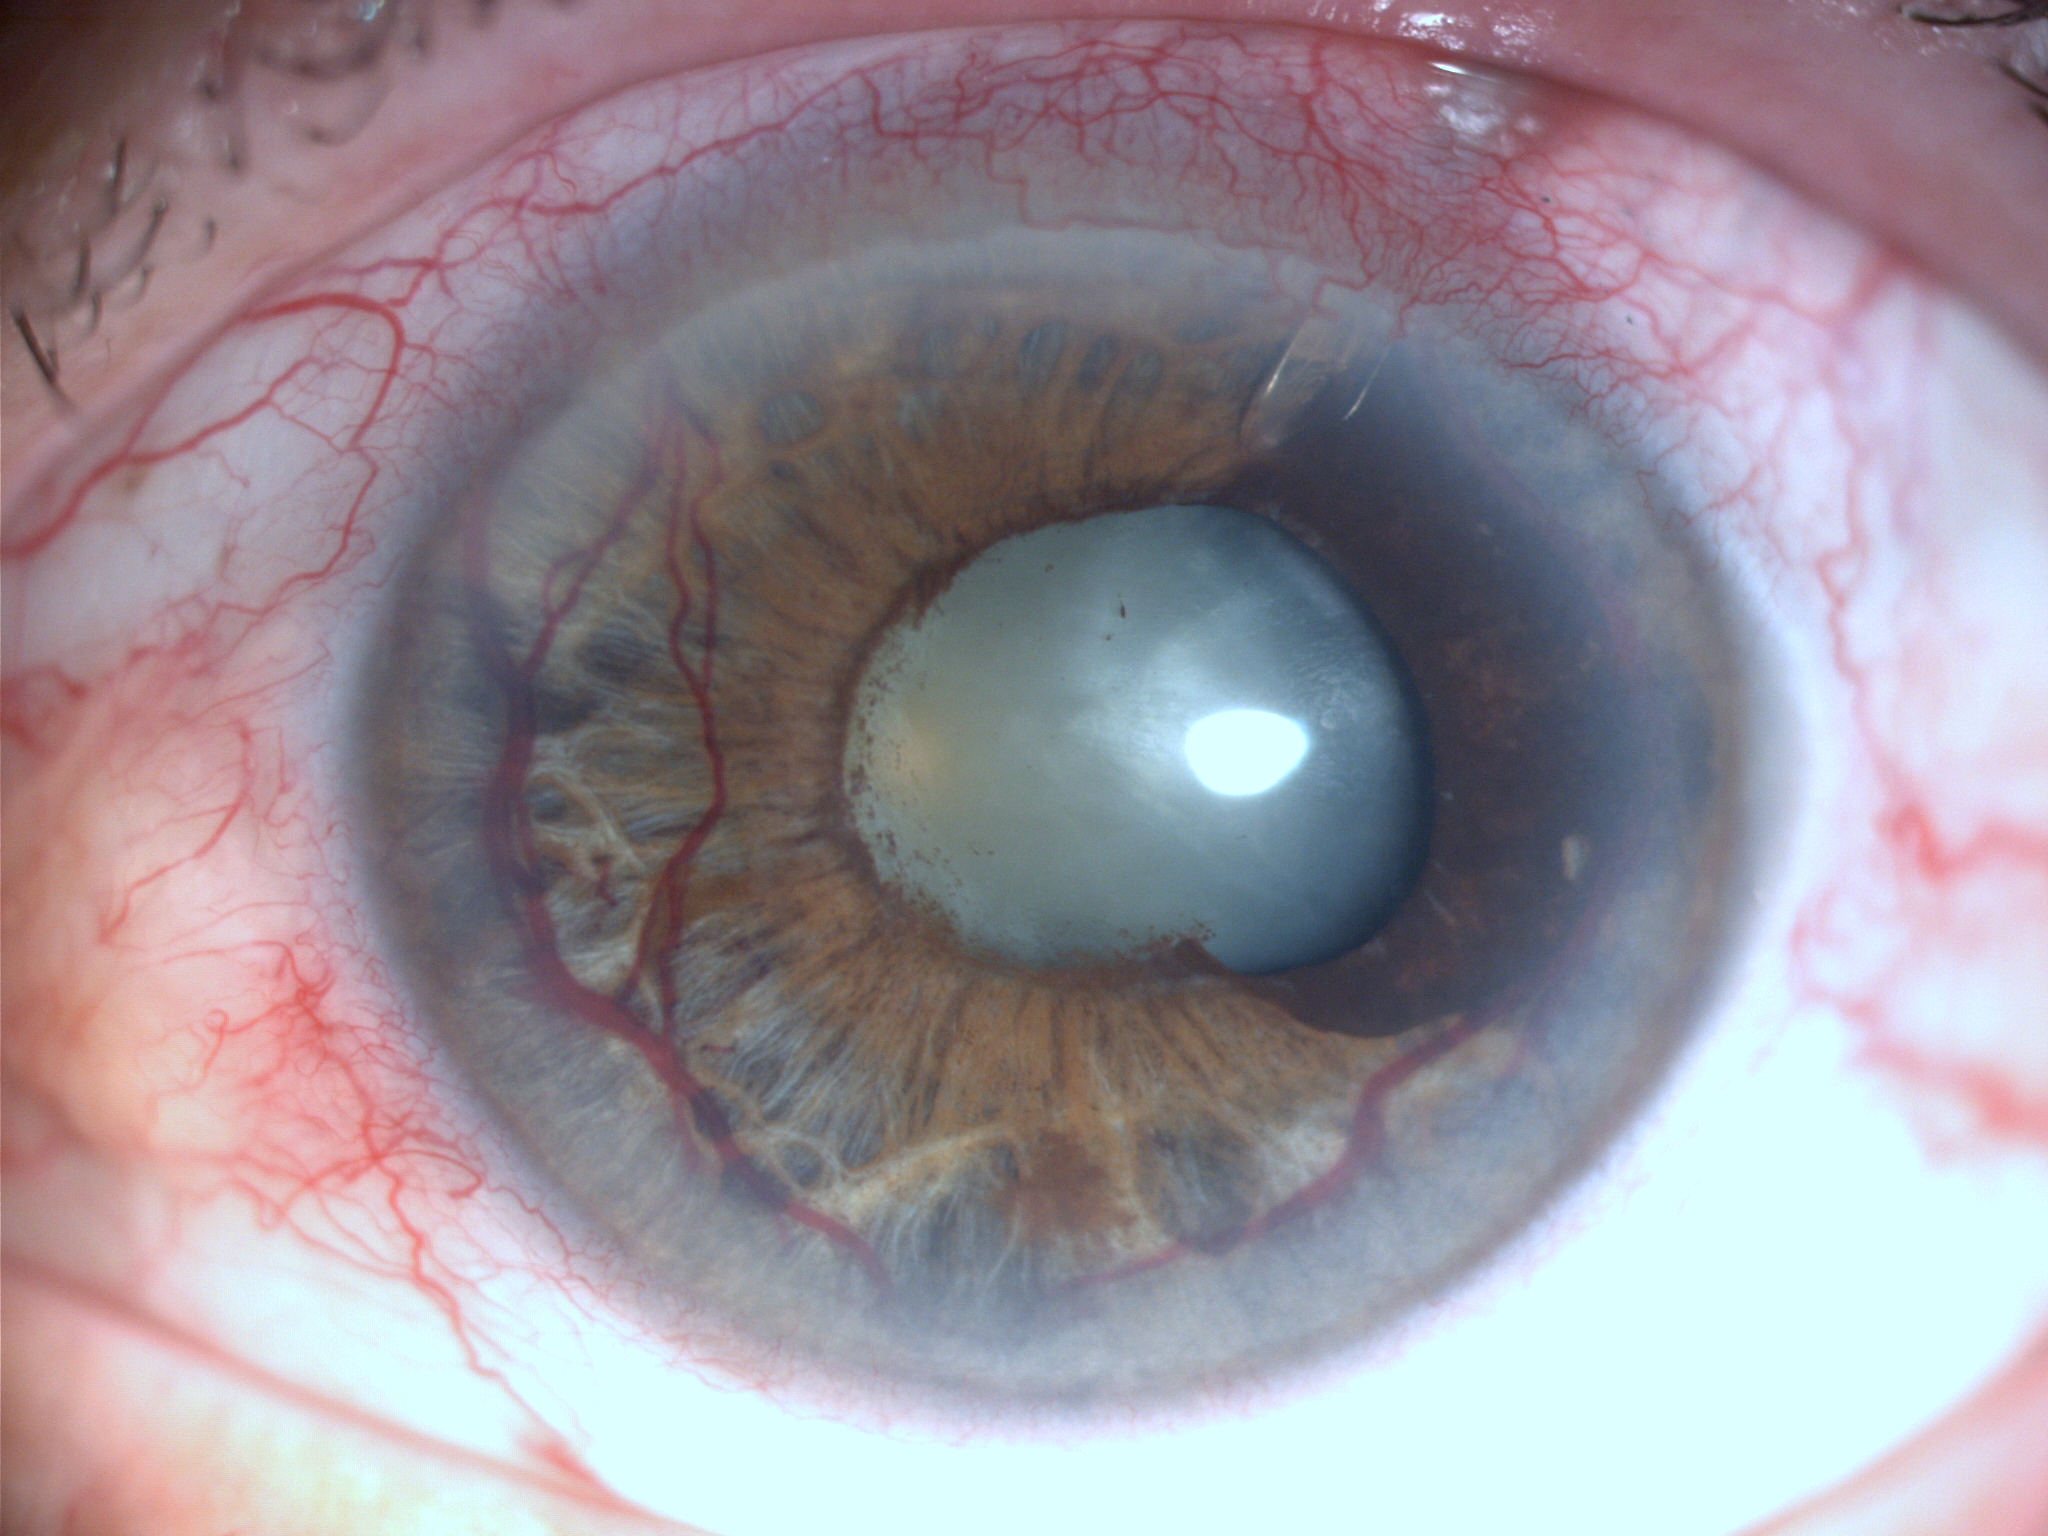

В 100% (28/28) случаев отмечена неоваскуляризация радужки и угла передней камеры (рис. 2). Интраоперационная геморрагия из новообразованных сосудов угла передней камеры и радужки в основном возникала на этапе пункции в зоне планируемой имплантации трубочки или при синустрабекулэктомии, а также за счет быстрого опорожнения передней камеры. Гифема в раннем послеоперационном периоде отмечена в I группе в 30,7% (4/13) случаев, во II группе – в 26,6% (4/15) случаев. Промывание передней камеры и тампонада новообразованных сосудов введением вискоэластика выполнены у всех пациентов I и II группы. Применение высокомолекулярного вискоэластика на этапе пункции передней камеры глаза позволило избежать геморрагических осложнений в оставшихся случаях.

2. Клапан Ahmed у пациента с неоваскулярной глаукомой и рубеозом радужки | |